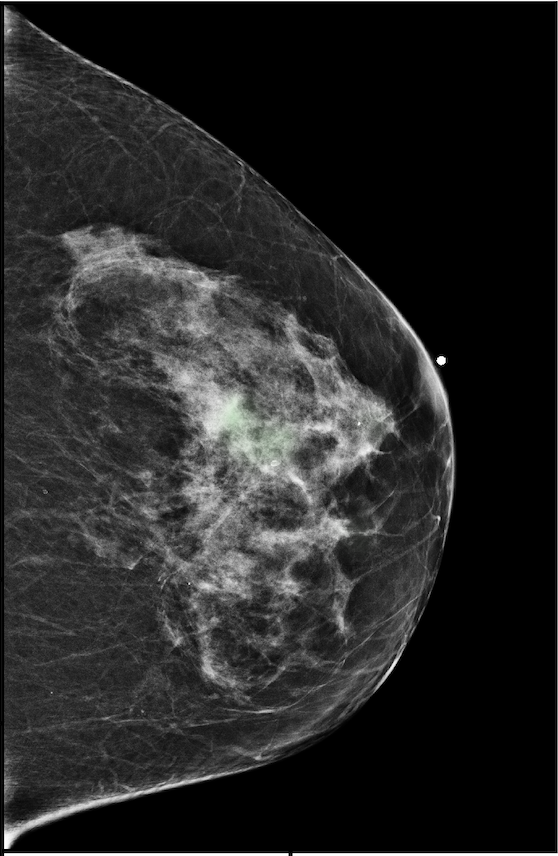

|

![]() |

| R-CC | L-CC |

| R-MLO | L-MLO |

The NYU Breast Cancer Screening Dataset [78] includes 229,426 exams (1,001,093 images) from 141,472 patients.222Our retrospective study was approved by our institutional review board and was compliant with the Health Insurance Portability and Accountability Act. Informed consent was waived. Each exam contains at least four images which correspond to the four standard views used in screening mammography: R-CC (right craniocaudal), L-CC (left craniocaudal), R-MLO (right mediolateral oblique) and L-MLO (left mediolateral oblique). An example is shown in Figure 3.

For all exams matched with biopsies, we asked a group of radiologists (provided with the corresponding pathology reports) to retrospectively indicate the location of the biopsied lesions. This way we obtained the segmentation labels: where if pixel belongs to the benign/malignant findings. An example of such a segmentation is shown in Figure 3. In all experiments (except for experiments in Section 3.6 that assess the benefits of utilizing segmentation labels), segmentation labels are only used for evaluation. We found that, according to the radiologists, approximately of exams were mammographically occult, i.e., the lesions that were biopsied were not visible on mammography, even retrospectively, and were identified using other imaging modalities: ultrasound or MRI.